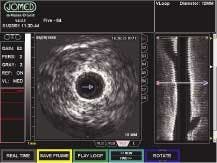

The In-Vision Gold imaging system interfaces to a medical fluoroscope in either a high- or low-resolution composite NTSC/PAL format (see Fig. 1). A Coreco Imaging (St.-Laurent, QC, Canada) Viper-RGB frame grabber synchronizes and digitizes the input signals at either 8 or 10 bits. This single-slot, color and monochrome video-acquisition and processing board for the PCI bus features 40-MHz acquisition and can acquire and transfer images in real time to system memory. It provides RGB acquisition, three 10-bit ADCs, and a signal-to-noise ratio of 55 dB. When PCI bus traffic is heavier than normal, the frame grabber buffers image data into local memory temporarily so that processing speeds are not affected.

"We chose the Viper-RGB frame grabber because it enables real-time video output of 30 frames/s. Medical personnel can display patient information directly on a fluoroscopy monitor or store the data in digital format so that they can review it at any time on their PC monitors," says Lindsay.

The frame-grabber data are transferred via a Coreco Sapera API software interface to another Viper-RGB frame grabber and then on to an In-Vision application board. The Sapera software library offers more than 300 image-acquisition, processing, and analysis functions. The application board transfers the fluoroscopic data via Sapera's DirectDraw software to the system's video memory and 17-in. monitor (see Fig. 2).